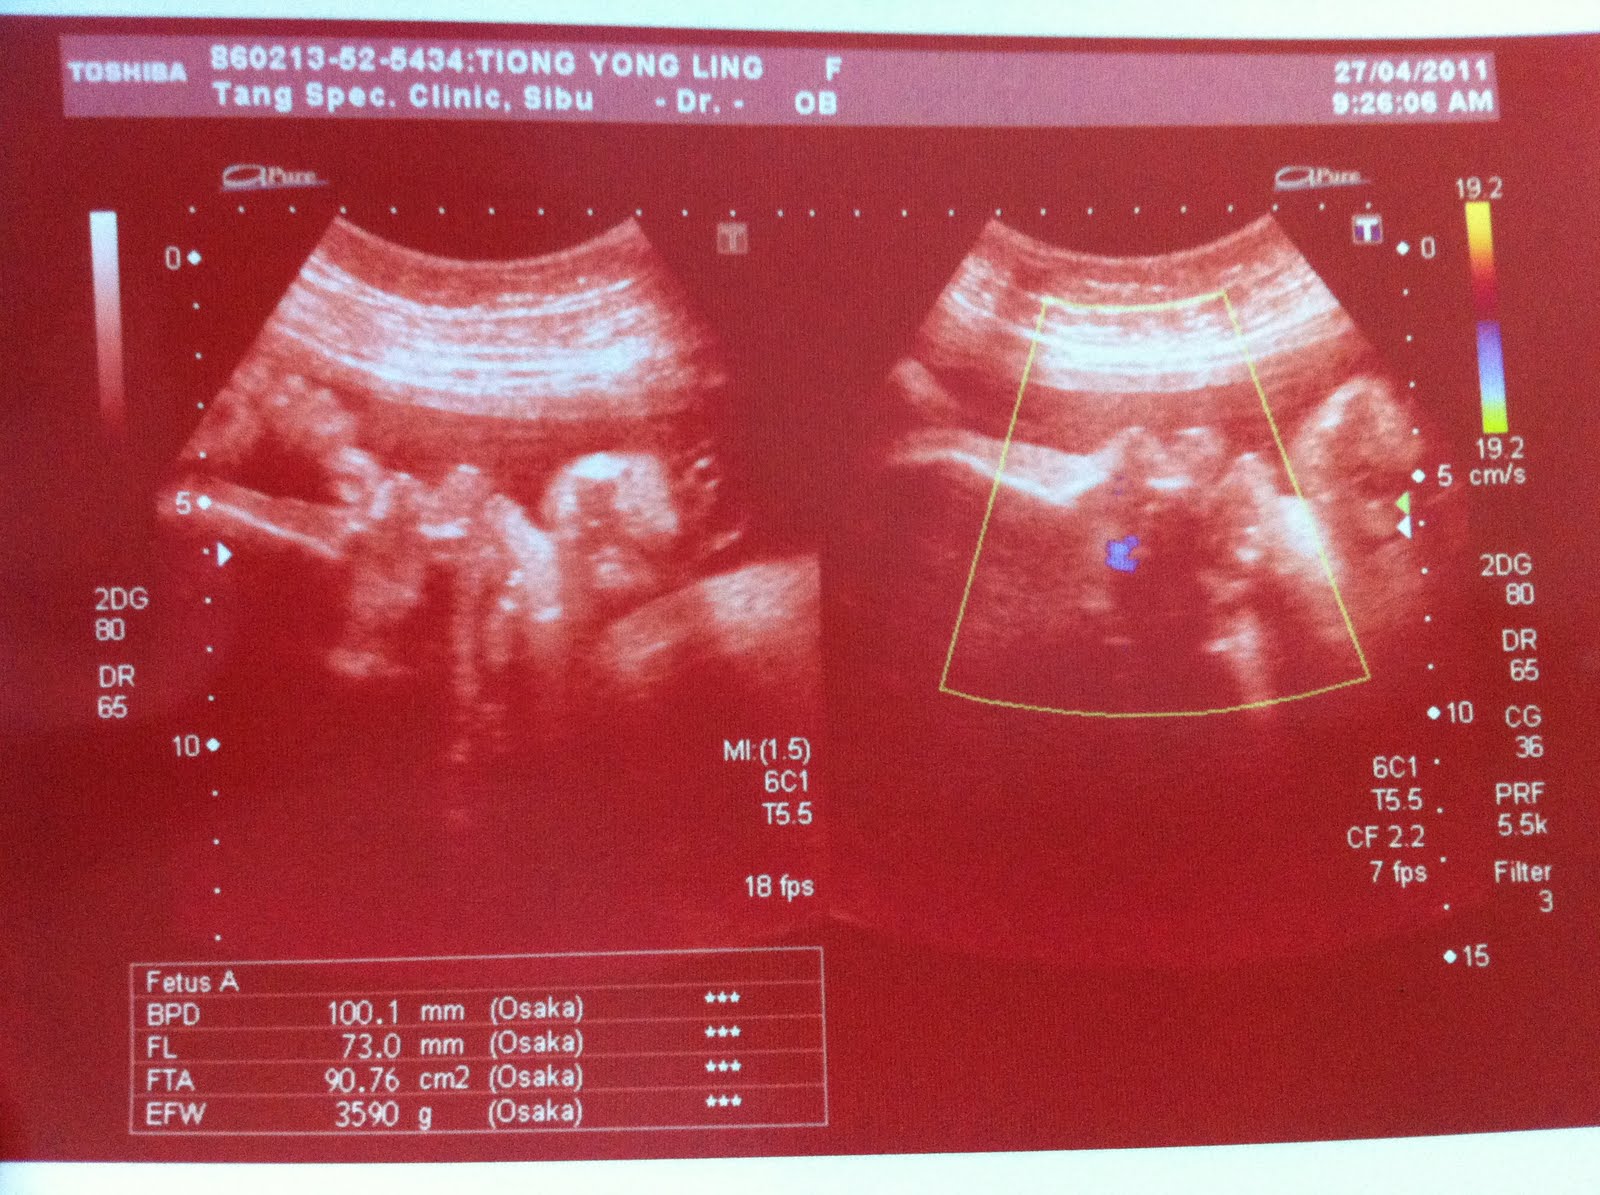

【27.04.11】

37周产检。

这是Dr Tang Scan 的.